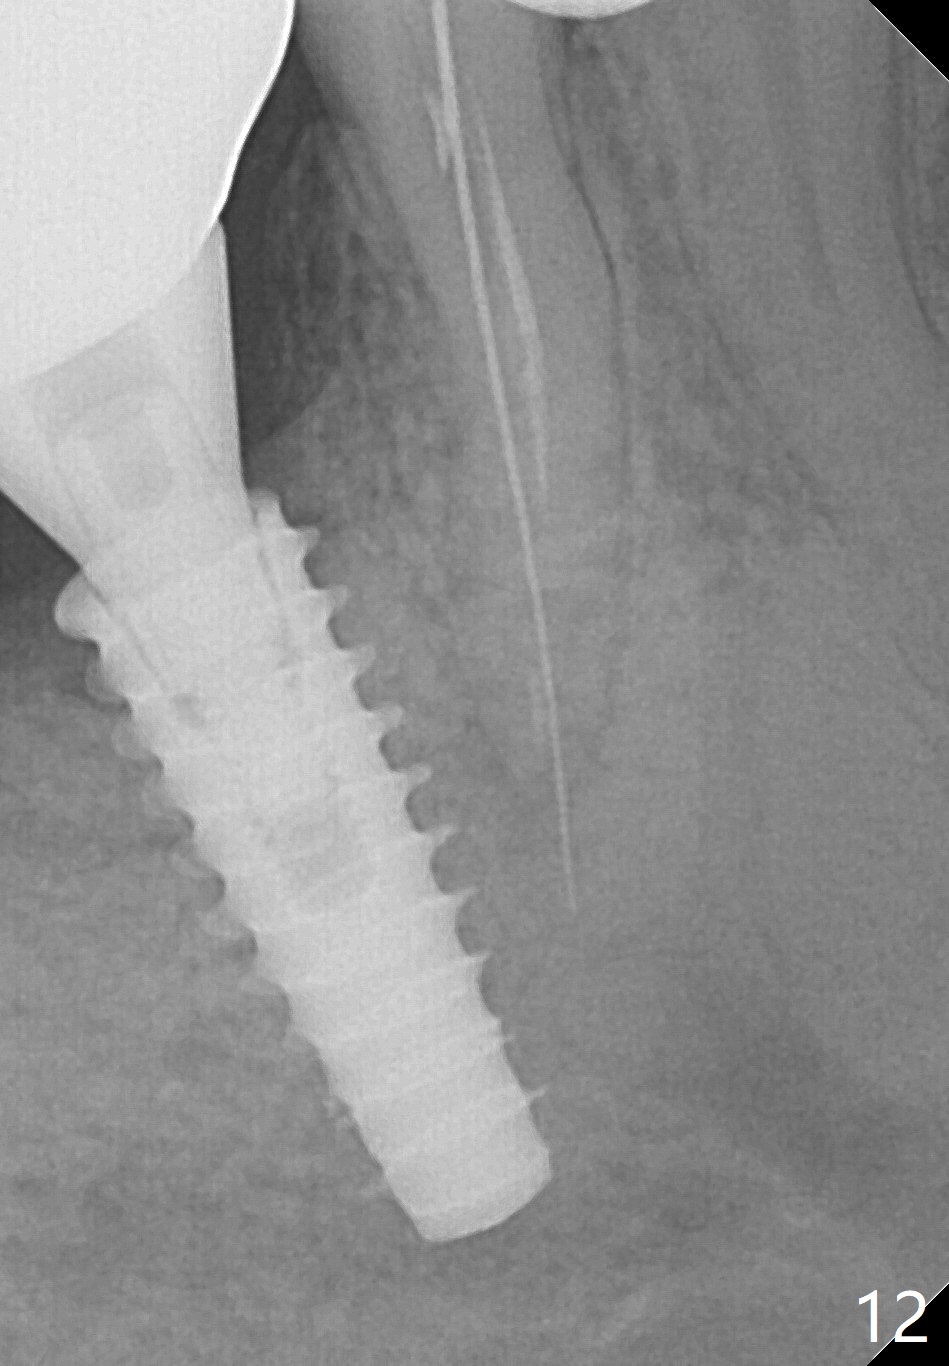

Bone graft seems to sink down and becomes denser 3 months postop (Fig.6 arrow). The bone continues being denser 5 months postop (Fig.7). There is periapical radiolucency of the tooth #29 (^). RCT is done (Fig.8). The pain persists 2 weeks postop (Fig.9,10). There is no missing canal (Fig.9). The apex is close to the implant (Fig.9 *). Apicoectomy will be performed if needed. It appears that the implant is also placed buccal (Fig.10 <) and/or the implant too large for the site. Therefore there should be a 2-3 mm buccal gap before and after implant placement. Separation and reflection of the buccal flap allows better visibility. The pain persists 1 month post RCT and 6 months post implant placement. RCT retreatment is initiated (Fig.11,12) with placement of Calcium Hydroxide paste after redebridement with 30/.04 rotary file at 23.5 mm (.5 mm longer than the earlier RCT, Fig.13). RCT retreatment finishes with apparent transportation and extrusion in 4 weeks (Fig.14,15), followed by apicoetomy (Fig.16,17) (20 days later)). Discomfort remains 2.5 months postop (Fig.18). Keep watching.